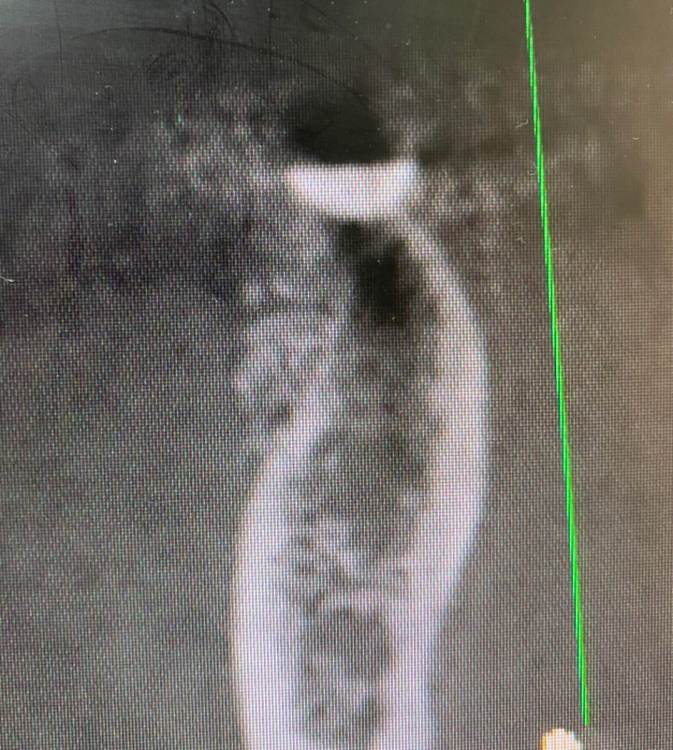

Irouil Опубликовано 11 июля, 2022 Поделиться Опубликовано 11 июля, 2022 (изменено) Не понял - почему недозаглубен? Оба винтыа где-то на 1мм под краем гребня Изменено 11 июля, 2022 пользователем Irouil Ссылка на комментарий

Irouil Опубликовано 11 июля, 2022 Поделиться Опубликовано 11 июля, 2022 (изменено) По фото невозможно понять что там было заглубленно и что нет, на рентгене картина объективнее Я вижу из возможных косяков пл хирургии только избыточно лингвальное позиционирование платформы у одного из винтов, из-за чего стенка очень тонкая - если там случилась резорбция, то иллюзию недозаглубения на фото она вполне может создать К тому же, ТС раньше рассказывал что часто идёт на тунельную твердотканную аугментацию при имплантации в таких случаях, если тут тоже - то для меня неточное позиционирование объясняется именно тунельным подходом и ограниченным обзором по такому поводу. Это, в сущности, единственное, что останавливает меня самого попробовать подобную аугментацию как альтернативу минисосиджу. Но надо услышать ТС, это только мои догадки Изменено 11 июля, 2022 пользователем Irouil Ссылка на комментарий

Irouil Опубликовано 11 июля, 2022 Поделиться Опубликовано 11 июля, 2022 @TIGER какие у Вас на этом фото объективные ориентиры, позволяющие оценить уровень погружения импланта? Такие, чтобы были точно в одной плоскости с оцениваемым положением платформы и в параллельной плоскости к матрице камеры? Это же все равно что объем альвеолярного гребня в области альвеолярной бухты оценивать по плоскостным снимкам Ссылка на комментарий

Irouil Опубликовано 11 июля, 2022 Поделиться Опубликовано 11 июля, 2022 @TIGER ладно, давайте подождём мнения Игоря, на рентгене (который был ДО резорбции и явно объективнее, чем фото ПОСЛЕ неё, да ещё и не в академической проекции) я явного недозаглубения не вижу, хотя глубить, вроде бы, ещё было куда и тут вопрос скорее в том, почему ТС не решил перестраховаться 1 Ссылка на комментарий

Astronaft Опубликовано 12 июля, 2022 Поделиться Опубликовано 12 июля, 2022 (изменено) 06.07.2022 в 14:28, колесников сказал: Протокол отработан как автомат Калашникова,платформа относительно Зенита и вершины гребня,высота уступа,наличие и ширина прикреплённой слизистой. Далее процесс запускается вспять и через два года наблюдаем прирост кости на скосе гребня. Это хорошай заговор-пожелание. В жизни часто не так. По одной простой причине общее здоровье человека влияет намного сильнее. Пародонтологический статус - если есть карманы хоть 5-6мм где-то во рту риск пери-имплантных явлений возрастает. Микробиота слюны, вязкость, диета, качество гигиены, обший воспалительный фон- это сфера влияния пациента. Качественное местное исполнение это хороший фундамент - только одна из составляющих. Астра Профаил - укороченный, асимметричый конус. 3мм с одной стороны, 2мм с другой. Конфигурация перелома закономерна - сами абатменты раскололи высокую стенку от низкой. Я бы предположил что тещины первичны, резорбция это следствие. Изменено 12 июля, 2022 пользователем Astronaft 2 4 Ссылка на комментарий